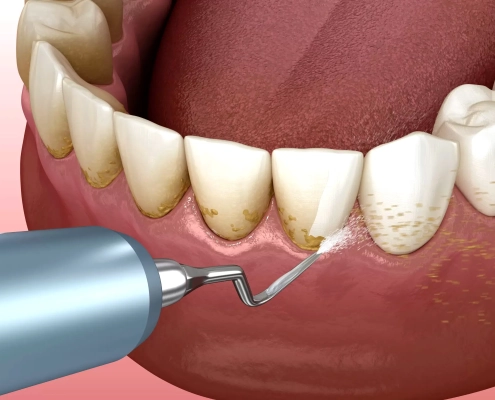

جرمگیری دندان در شمال تهران؛ لبخند واقعیتان را همین امروز برگردانید ✨ | رزرو نوبت فوری

بهعنوان متخصص دندانپزشک زیبایی، جرمگیری دندان در شمال تهران ی…

جرمگیری دندان در ولنجک — چه زمانی، چگونه و چرا بیماران خاص منطقه ۱ به کلینیک من مراجعه میکنند؟

جرمگیری دندان در ولنجک یکی از مهمترین خدمات تخصصی برای حفظ سلامت لثه، …

جرمگیری دندان در زعفرانیه؛ ترکیب سلامت با زیبایی، علم و تجربه

من دکتر سید رضا خسروانی، متخصص دندانپزشکی ترمیمی و زیبایی در ولنجک، جرمگیری …